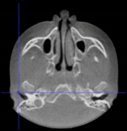

Three points determined the Acta plane: O, F right (FR), and F left (FL) (Table 2). Point O is the midpoint between the most craniodorsal point of the dorsum Sella and the most posterior dorsal point of the Basion in the midsagittal plane (Figure 1). Both points F are a result of the intersection between two lines: the line that connects the most inferior points of the lower orbital margins, right and left, and a line perpendicular to this line that runs through the most external points of the orbital margins, right and left (Figure 2). The new transverse reference plane, the Acta plane (Figure 2), is created by connecting the O-point (Figure 1) with FR and FL (Figure 2).

Figure 1.

Point O (green dot) is the midpoint between the dorsum Sella (Se) (red dot) and the Basion point (Ba) (yellow dot).